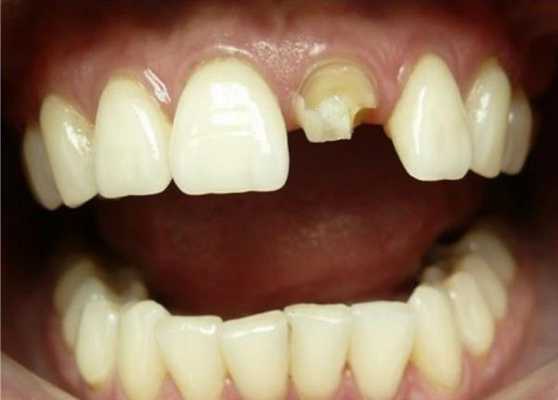

Пациентка М., 35 лет, обратилась в клинику с жалобами на расцементировку коронки из оксида алюминия на 2.1. Объективно: коронка имела подвижное положение на культе зуба 2.1 и без усилий извлеклась. Отмечался откол 1/3 культи зуба (внутренняя часть коронки была заполнена отделившимся фрагментом).

Дефект культи 2.1 зуба

Зуб в прошлом подвергался эндо лечению с последующим восстановлением с использование полимерного штифта. Отмечалось полное сохранение полимерного штифта на всем протяжении. Откололась только внутренняя поверхность коронки с фрагментом культевого материала.